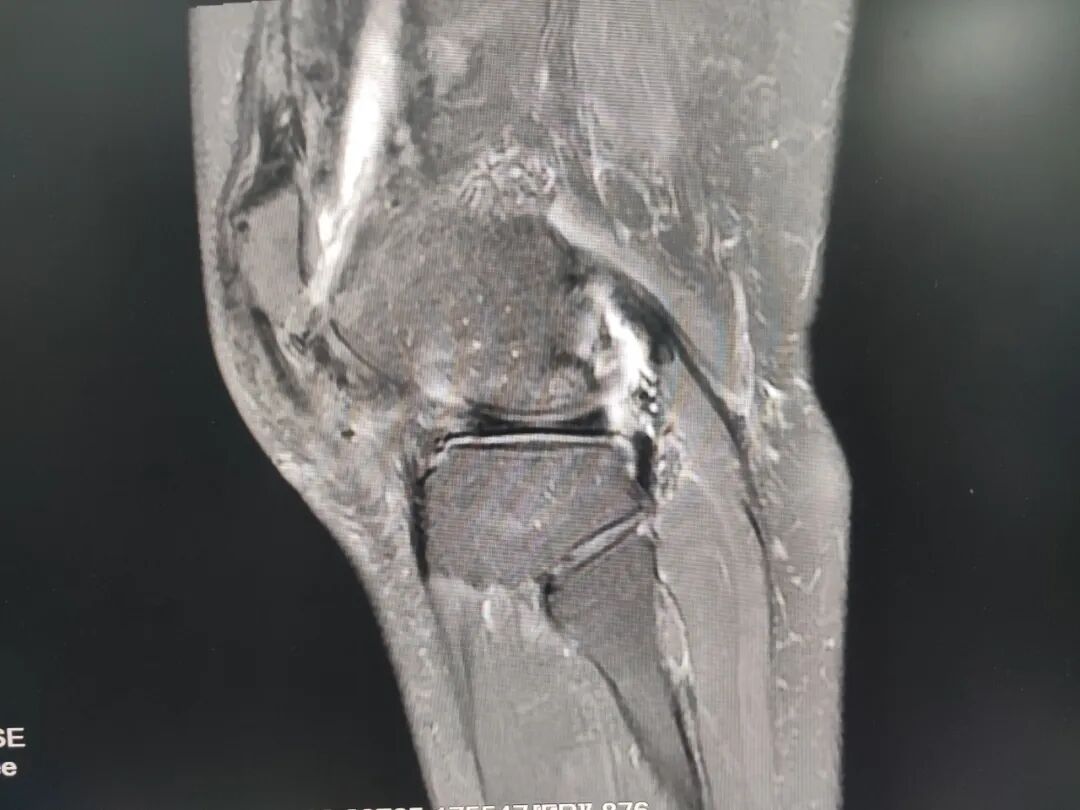

关节疼痛难忍?放疗精准“灭火”

精准,是治疗的关键